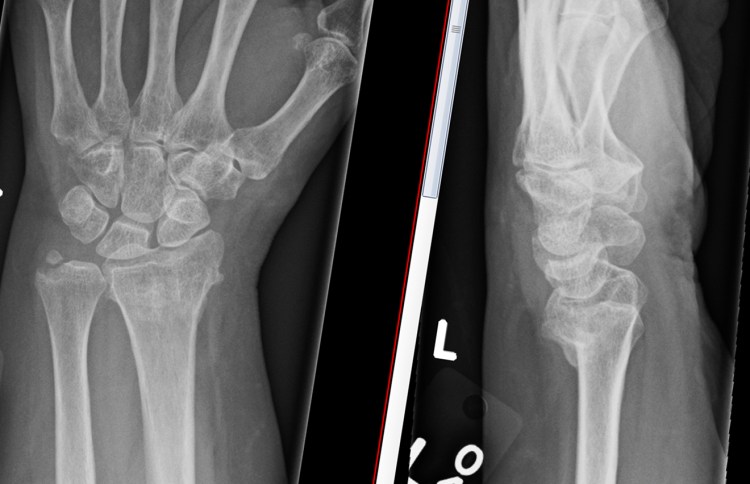

The surgery involves making an incision over the area of the malunion, and using a fine saw, the bone is divided. The bones are then repositioned in a more normal alignment and usually a small plate is used to fix the bone in its new position. On a normal side view xray (lateral view), if you draw a line up the middle of the radius bone, then this line should continue through the middle of the capitate bone. In a malunion, the continuing line does not pass through the middle of the capitate. The aim of surgery is primarily to restore this line.